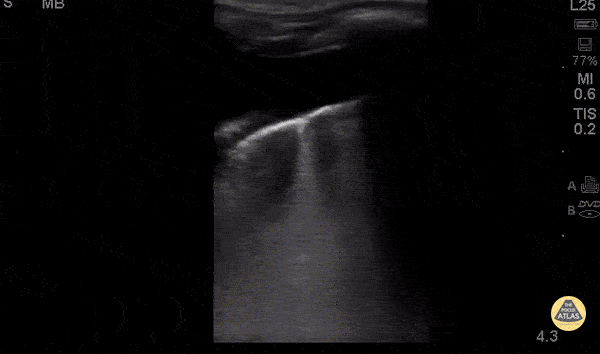

3 yo m previously healthy UTD with vaccines. 5 days of cough and fevers. 3 days of abdominal pain, acutely worsening day of presentation with 1 episode of NBNB emesis. Febrile tachypneic and hypoxic to 91% on RA. CXR: white out of right lung. POCUS: large right sided effusion. Hepatization with air bronchograms on the right lateral view. Dr. Isaac Gordon - Kings County Pediatric Emergency Medicine